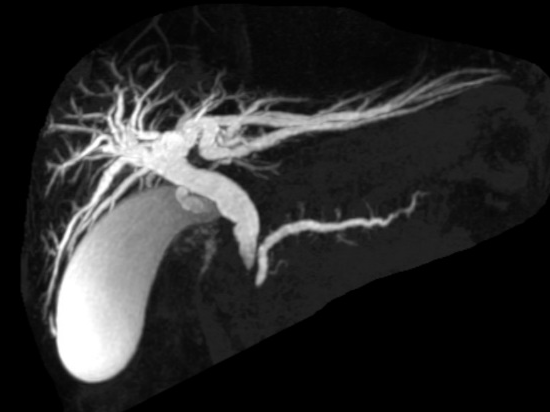

图5A

图5B

典型病例5:

男,60岁,上腹痛。图A:增强T1WI示胰头部团块状弱强化病灶。图B:MRCP示低位胆道梗阻征象,可见肝内外胆管扩张,胆总管扩张,胆囊增大,胰管扩张。